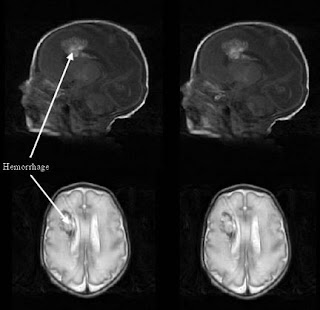

Sagittal and coronal US of a grade 2 hemorrhage

Intraventricular hemorrhage (IVH) with periventricular hemorrhagic infarction (PVHI).

Severe or grade III hemorrhage (subependymal with significant ventricular enlargement).